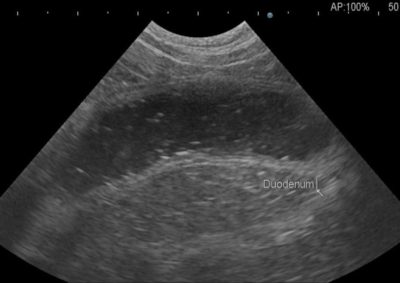

沈黙の胆嚢粘液嚢腫